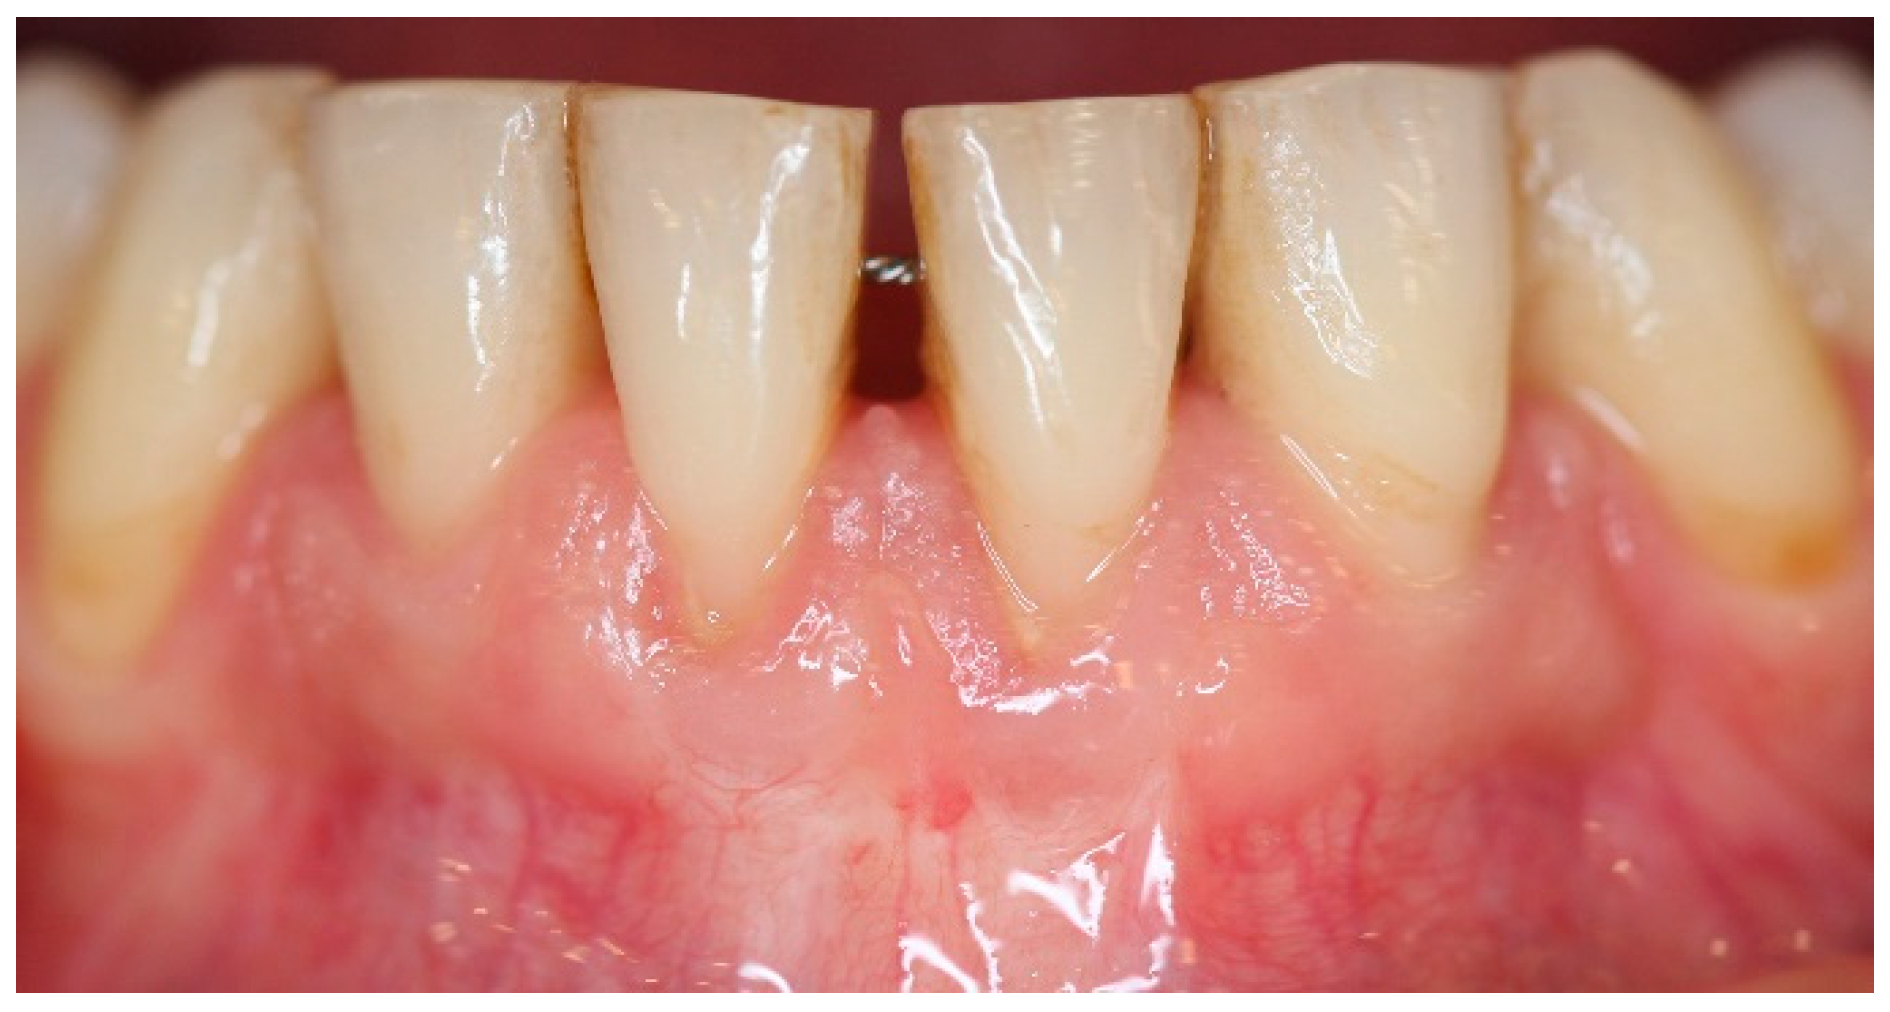

5. Materials and Methods

6. Results